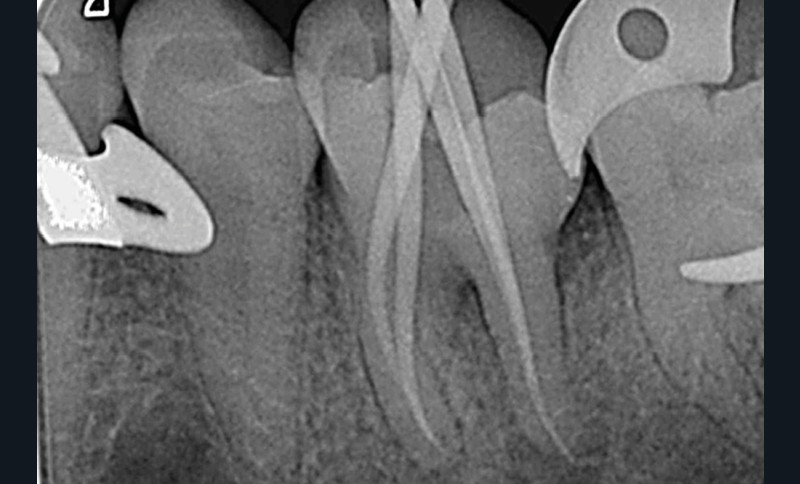

La mise en forme doit également s’adapter aux singularités anatomiques. Pour ce cas clinique, le canal mésio-lingual a été mis en forme en premier jusqu’à la longueur de travail. Puis le test du cône a été réalisé (fig. 4 et 5) afin de voir si les deux canaux se rejoignaient. Ces deux canaux se rejoignant à 3 mm de l’apex, le canal mésio-vestibulaire a été mis en forme à sa longueur de travail moins 3 mm afin d’éviter la zone de confluence et le risque accru de fracturer un instrument. De plus, cette mise en forme longueur de travail-3 mm a son importance pour la précision de l’obturation et l’ajustage des cônes. Pour le canal distal, qui était un canal « en 8 », nous appliquons le même raisonnement que pour les canaux mésiaux, avec un canal principal, test du cône, et ajustage des maîtres-cônes (fig. 6).